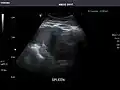

Spleen -